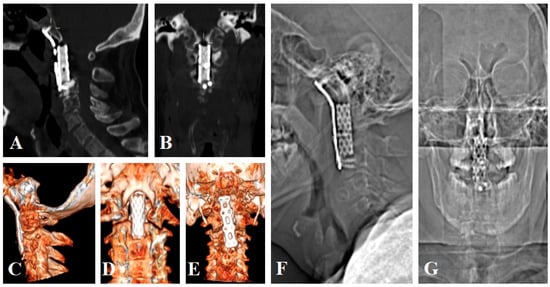

3.1.2. Clinical Case 2

3.1.3. Clinical Case 3

3.3. Surgical Technique and Radiological Follow-Up